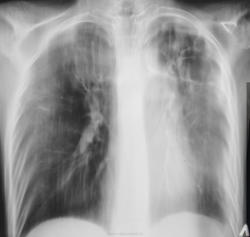

Прошел год, пациент значительно потерял в весе, температура около 38 градусов, кашель с мокротой и был доставлен в рентгеновский кабинет на носилках.

"Ой"! Воскликнули фтизиатры, это наше! На носилках пациент был срочно госпитализирован в областную туб больницу в тяжелом состоянии. Лечение, со слов фтизиатров, было не легким, так сказать - "на грани", пациент был прооперирован.